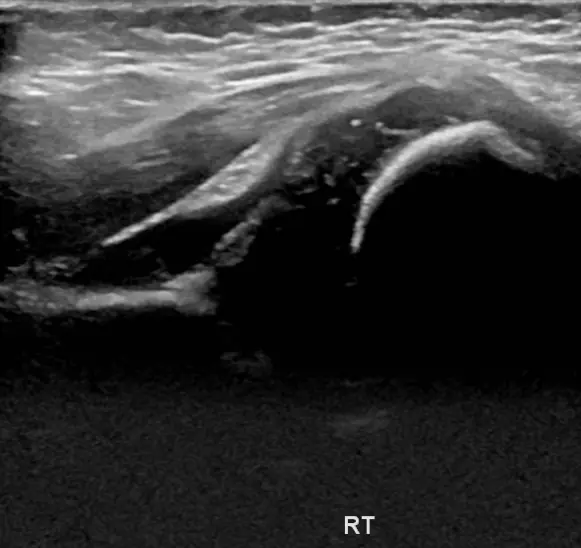

안녕하세요! 오늘은 아기 허벅지 주름이 비대칭이거나 이상하게 보일 때 꼭 체크해야 하는 내용을 알려드릴게요. 신생아나 영아의 허벅지에 자연스럽게 생기는 주름이지만, 깊이나 위치가 다르면 발달성 고관절 탈구의 신호일 수 있어요. 이 질환은 태어날 때부터 허벅지뼈가 골반에 잘 맞물리지 않는 상태로, 방치하면 걷기 어려움이나 다리 절름발이로 이어질 수 있어요. 다리 길이 차이, 다리 움직임의 이상, 걷기 시 불편함 등 증상이 있다면 빠른 검사가 필요합니다. 초음파 검사는 4주에서 6개월 사이에 가장 효과적이며, 방사선 걱정 없이 안전하게 아기 허관절 구조를 확인할 수 있어요. 조기 발견 시 간단한 치료로 정상 성장 가능하니, 아기 허벅지 주름이 이상하게 보인다면 꼭 전문가의 검진을 받아보세요. 건강한 성장과 걷기를 위해 작은 관심이 큰 차이를 만듭니다.

아기의 허벅지 주름이 비대칭이거나 다리 길이 차이, 움직임 이상이 보인다면 빠른 검진이 중요합니다. 초음파 검사는 안전하고 정확한 방법으로, 조기 치료를 통해 정상적인 성장과 걷기를 기대할 수 있어요. 부모님들이 작은 신호도 놓치지 말고 정기 검진을 챙기시는 게 좋아요.